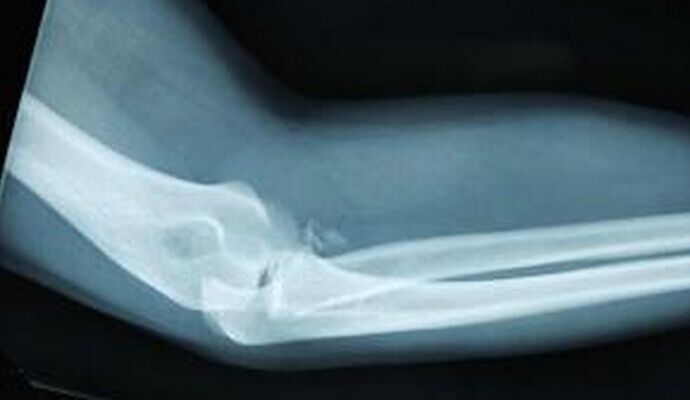

核心提示:桡骨小头半脱位又称达拉肘,是婴幼儿常见的肘部损伤之一。发病年龄1~4岁,其中2~3岁发病率最高,占62.5%。本病男孩比女孩多见,左侧比右侧多。当肘关节伸直,前臂旋前位忽然受到纵向牵拉时容易引起桡骨小头半脱位,有时幼...